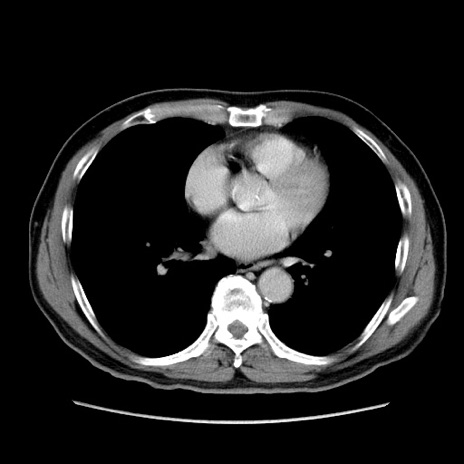

症例34(横断像)

【症例】60歳代 男性

【主訴】右鼠径部膨隆

【現病歴】1年程前より右鼠径部膨隆あり。自己にて還納可能だったため放置していた。3時間前より右鼠径部の脱出を認め、還納困難となり受診。

【既往歴】高血圧

【身体所見】右鼠径部に小児頭大の膨隆あり。弾性硬であり、用手還納は困難。左鼠径部にも膨隆を認める。脱出はなし。

【データ】WBC 15500、CRP 測定なし